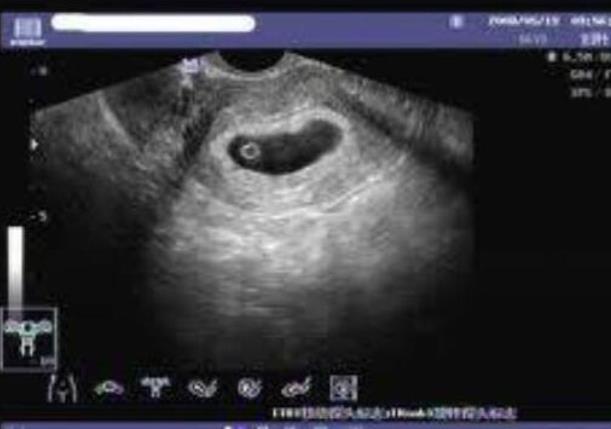

大家在选择做试管婴儿这项手术的时候,要综合各个情况来进行有效的分析,其实第一代试管婴儿技术相对来说都是非常不错的,我们要做好体外的肾经以及胚胎的移植,而且这也是最常见的技术,针对于女性患者存在输卵管堵塞或者是子宫内膜异位症,还有排卵障碍所导致的不孕不育的问题同样也很重要,那么这样的一项技术就是把男性取出的精子和女性的卵子在体外进行筛选的一个过程。

当我们要选择做试管婴儿这项手术的时候,大家要选择第三代试管婴儿技术,这样的一项技术针对的都是担心的遗传病或者是染色体遗传病的遗传问题的患者,这一项技术就是通过第一代试管婴儿技术或者是第二代试管婴儿技术取得可用胚胎之后,然后在胚胎移植之前对于早期的胚胎进行遗传学的筛查,这样的话就能够挑选整个染色体正常的胚胎进入到女性的宫腔中。